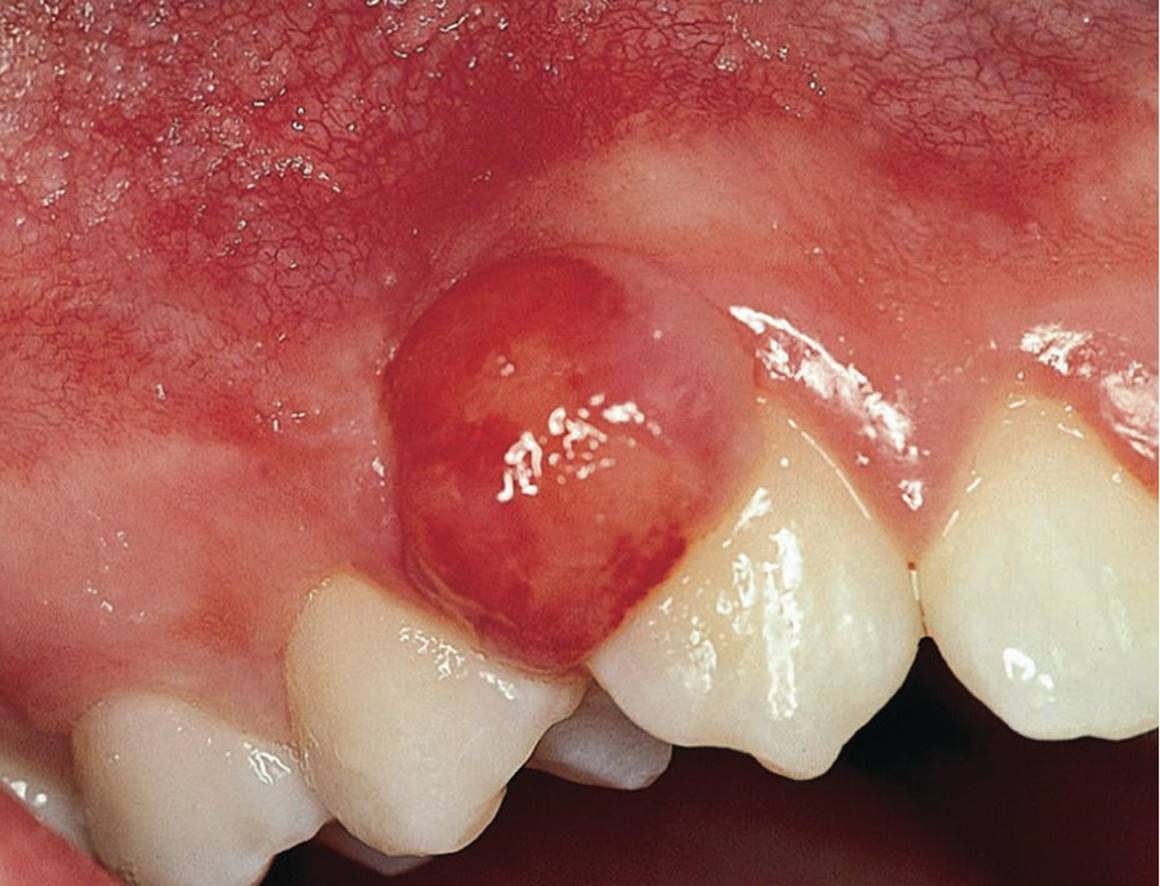

Epulides are by definition tumor‐like hypertrophic tissue formations located on the gingival mucosa. The etiology is often trauma or irritation in connection with tooth eruption or exfoliation. The size may vary from some millimeters up to several centimeters in diameter. They differ in surface texture, consistence and color, depending on the tissue composition. Pyogenic granuloma, peripheral calcifying granuloma, and peripheral giant cell granuloma (Figures 15.19, 15.20 and 15.21) are all examples of epulides. The treatment is excision, and the final diagnosis is confirmed by histopathologic analysis.

Figure 15.19 Pyogenic granuloma.